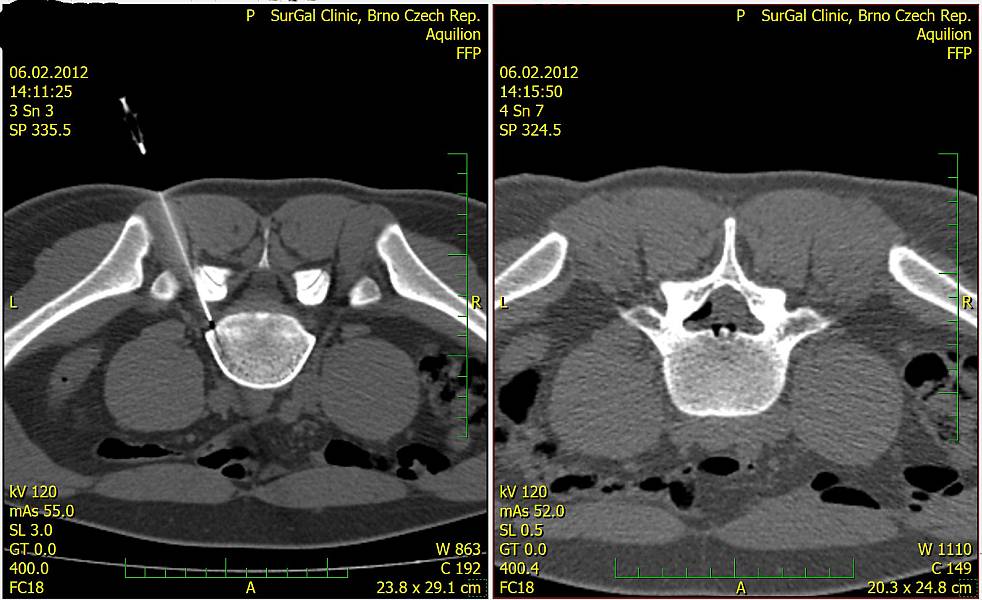

Zákrok se provádí pod navigací CT přístrojem za sterilních podmínek.

Bederní páteř:

- Pacient leží na břiše. Po základním vyšetření na CT a přípravě operačního pole lékař provede lokální anestezii kůže a podkoží a zavede tenkou atraumatickou spinální jehlu přesně k postiženému úseku páteře do epidurálního prostoru. Optimální cestu a umístění hrotu jehly určí lékař, cílová oblast je velmi malá a je tak pravděpodobné, že ověřování na CT bude opakované. Po ověření správné pozice jehly lékař aplikuje směs buď kyslíku a ozonu nebo anestetika, steroidního protizánětlivého léčiva a kontrastní látky, a provede se ověření distribuce léčiva.